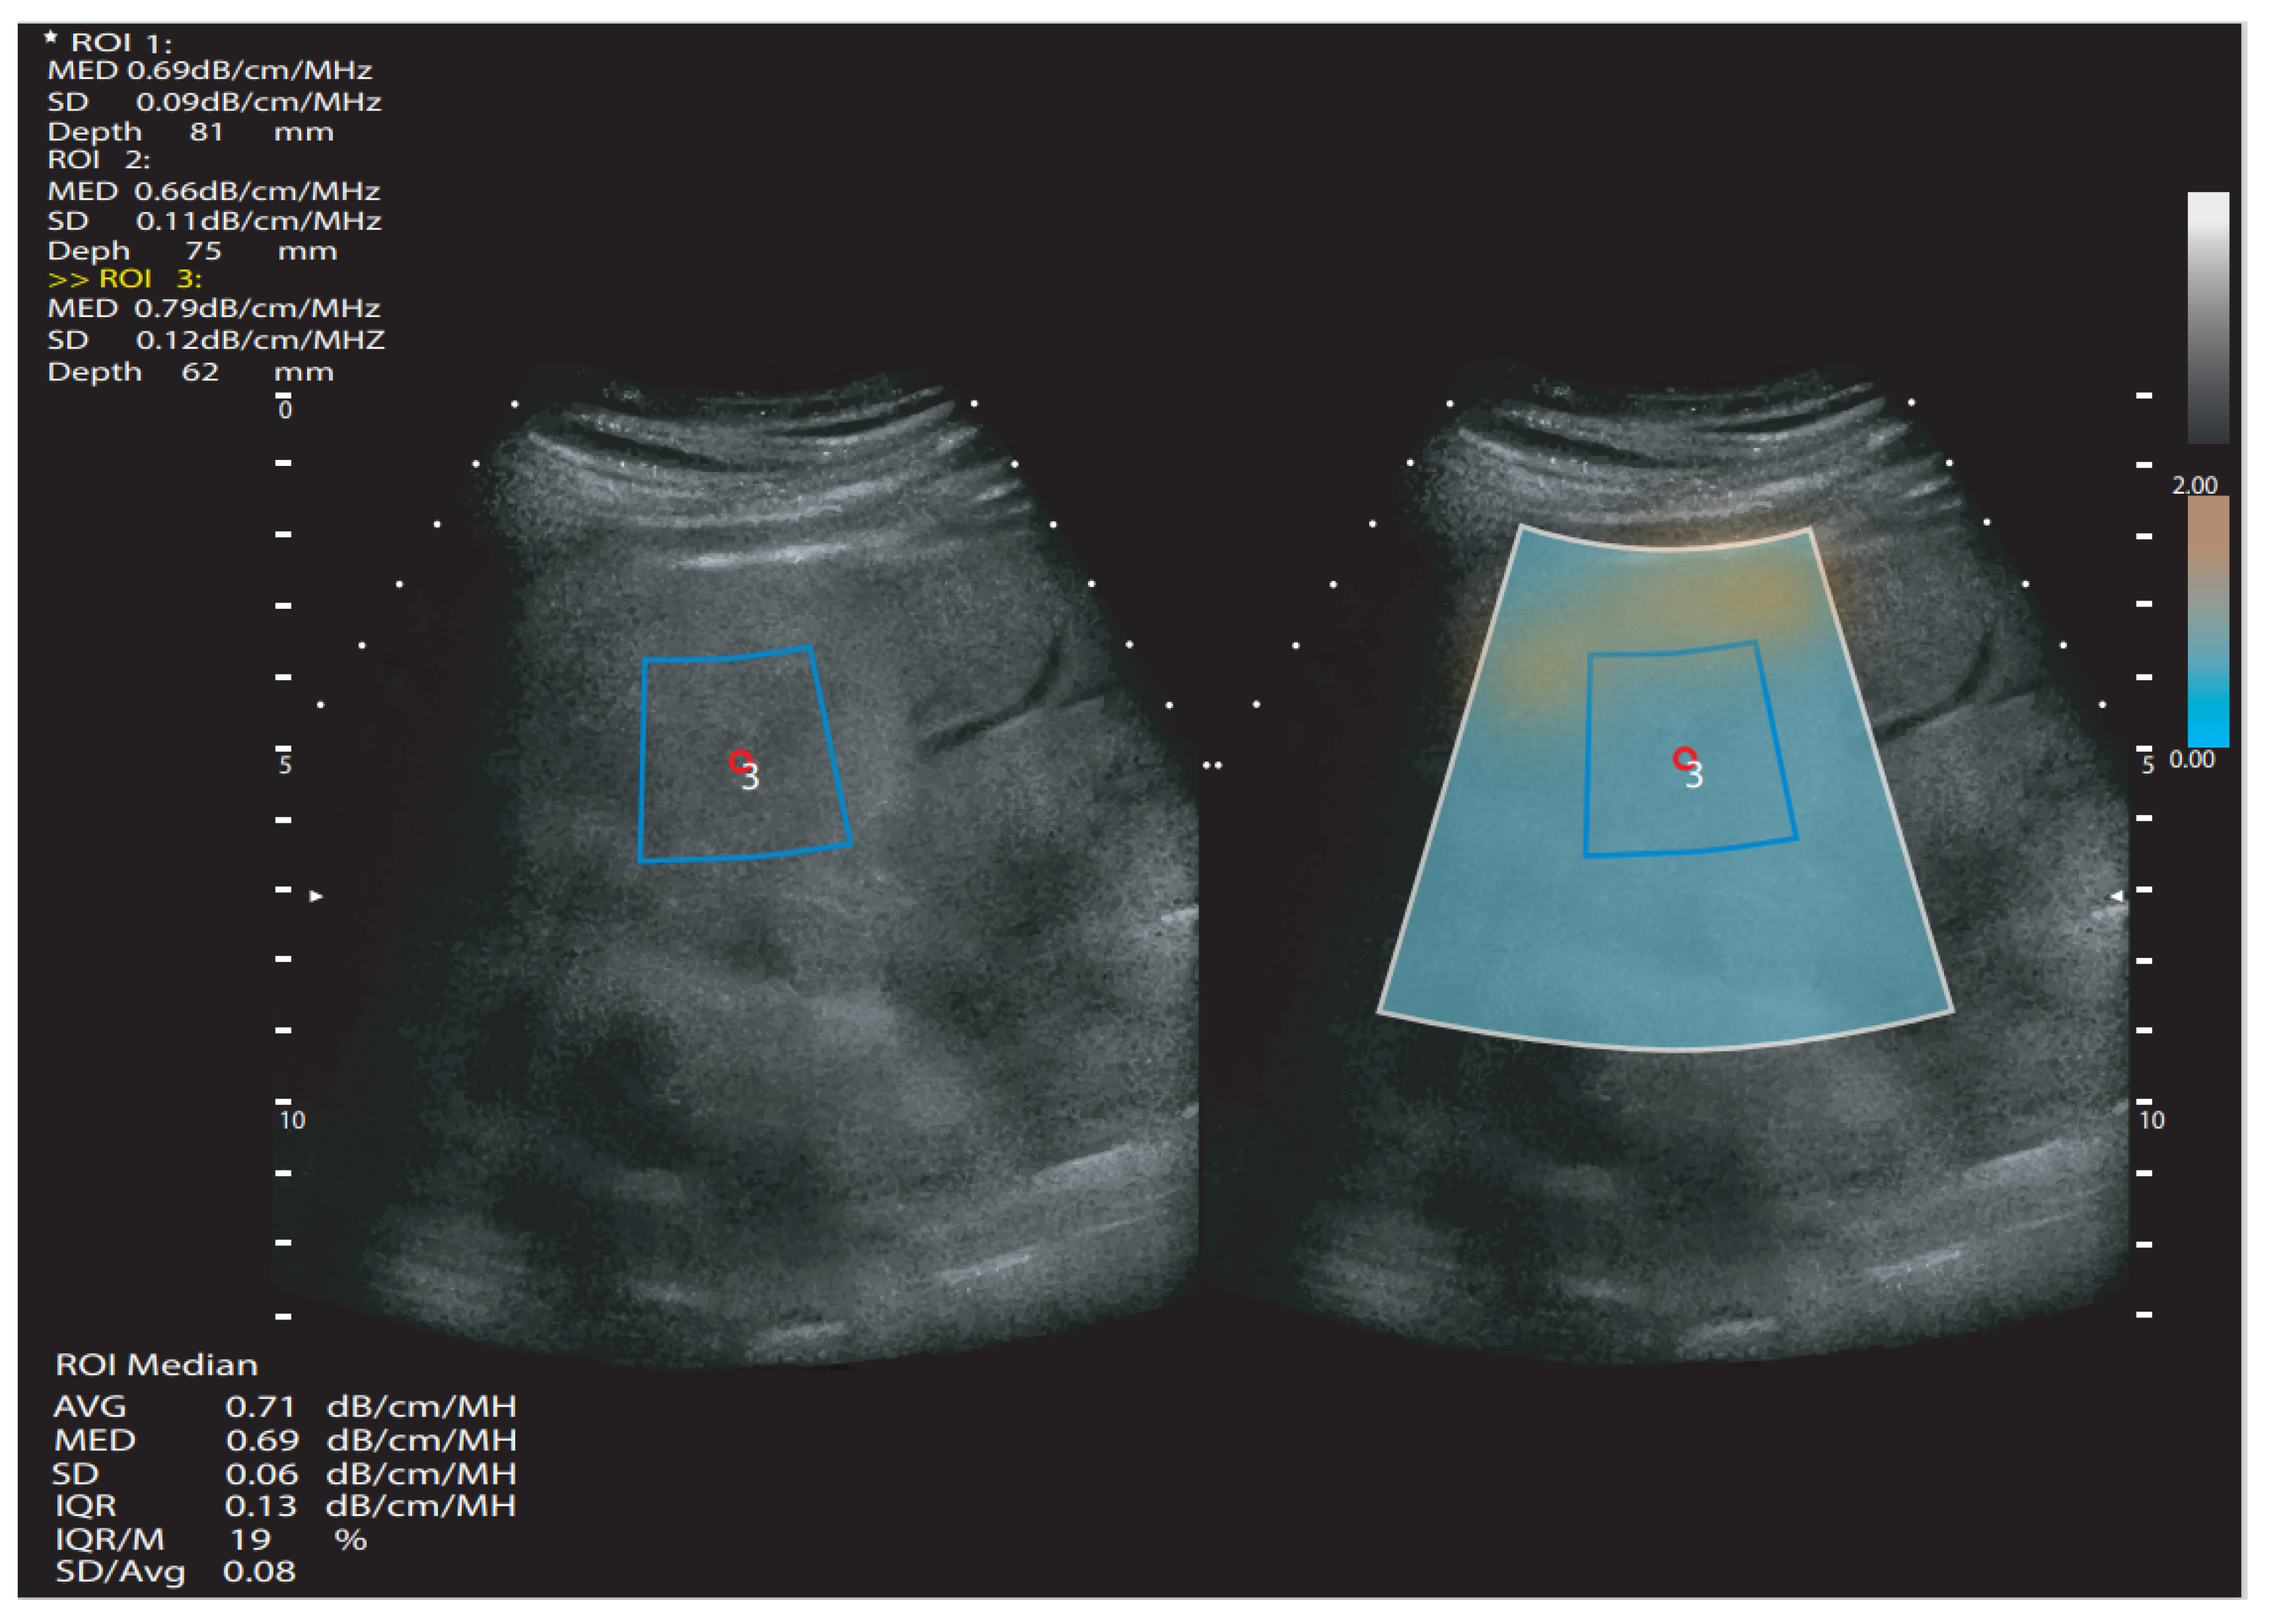

3.2. B-Mode qnUS Attenuation Techniques

Individual qnUS Applications Available on the Market

- TAI (Tissue Attenuation Imaging, Samsung Medison)